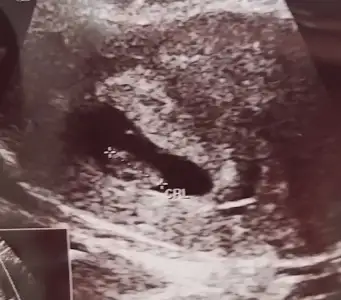

Kalp atışı için bhcg bakıldığını ilk defa duyuyorum. Burda kimsenin bakıldığında da sanmıyorum o kadar ileri safhada. Bence daha çok erken 5+4. 6+1 bile erken. 8 haftaya kadar yolu var. Bi dahaki gidişinde duyulur büyük ihtimalle bebeği görmüş ufakta olsa sonuç olarakKızlar merhaba dün yazmıştım düşük tehlikesi için bugün gittim doktora kese büyümüş şuan 17mm içinde çok minik bebeği gördüm dedi doktor etrafında kanama var dedi progestan kullanıyorum onun için. Yalnız beta hcg bakalım dedi 27700 çıktı doktor bu değerde kalp atışı olması gerekirdi dedi iki gün sonra tekrar bakıcaz değer artıyormu diye sizin beta kaçken duyulmuştu kalp atışışuan 5+4 haftalık ama ultrasonda 6+1 görünüyor

Benim beta baştan beri her ölçtürdüğümde günlük iki kat arttı yani fazla artıyordu ben gerçekten anlamadım daha önce de düşük yaptığım için çok korkuyorumKızlar merhaba dün yazmıştım düşük tehlikesi için bugün gittim doktora kese büyümüş şuan 17mm içinde çok minik bebeği gördüm dedi doktor etrafında kanama var dedi progestan kullanıyorum onun için. Yalnız beta hcg bakalım dedi 27700 çıktı doktor bu değerde kalp atışı olması gerekirdi dedi iki gün sonra tekrar bakıcaz değer artıyormu diye sizin beta kaçken duyulmuştu kalp atışışuan 5+4 haftalık ama ultrasonda 6+1 görünüyor

bende oyle hissediyorum ya allahm eli ayagi düz saglikli sihhatli dogmalarini nasip etsin tam zamanin da insallahBence biri kız biri erkek olacak öyle hissediyorum

Evet haklısın aslında ultrason çekilirken videoya aldık da dr oynattikca kese değişiyordu. Ramziye göre sence kız mi benim? Biraz geride kaldi görüntü gerciKesenin şeklinin hiç bi doğruluk payı yok. Ultrasonu azıcık oynatsa yuvarlak oluyor azıcık oynatsa yön değişiyor fasülye gibi oluyor. Yani ultrasonun açısıyla alakalı o. Bana ramzi daha gerçekçi geliyor. En azından doktor çalışmasıyla bulunmuş doğruluk payı yüksek

Ben de ilk 5.haftalikken keseyi ve bebeği gördüm, ayrıca kanama alani gözüküyordu ve normaldede kanamam vardi. Kalp için cok erken sakin üzülme positiv düşün. Bir hafta sonrasi kalp atışı duyuldu (o arada tekrar bi kanamam olmuştu acile gittim yine kalp atışı yoktu 6+1de) için ferah olsunKızlar merhaba dün yazmıştım düşük tehlikesi için bugün gittim doktora kese büyümüş şuan 17mm içinde çok minik bebeği gördüm dedi doktor etrafında kanama var dedi progestan kullanıyorum onun için. Yalnız beta hcg bakalım dedi 27700 çıktı doktor bu değerde kalp atışı olması gerekirdi dedi iki gün sonra tekrar bakıcaz değer artıyormu diye sizin beta kaçken duyulmuştu kalp atışışuan 5+4 haftalık ama ultrasonda 6+1 görünüyor

Ben bugun 6+2 yim kalp atisini duyduk, ilk oglumda 8.hafta ikincisinde 7 hafta da duyduk her bebegin döllenme zamani farkli oluyor, sıkma canını biraz daha bekle bakalim insallah duyarsin kisa sure icinde, ayrica kalp atisi icin artik beta baktiklarini duymadim hicKızlar merhaba dün yazmıştım düşük tehlikesi için bugün gittim doktora kese büyümüş şuan 17mm içinde çok minik bebeği gördüm dedi doktor etrafında kanama var dedi progestan kullanıyorum onun için. Yalnız beta hcg bakalım dedi 27700 çıktı doktor bu değerde kalp atışı olması gerekirdi dedi iki gün sonra tekrar bakıcaz değer artıyormu diye sizin beta kaçken duyulmuştu kalp atışışuan 5+4 haftalık ama ultrasonda 6+1 görünüyor